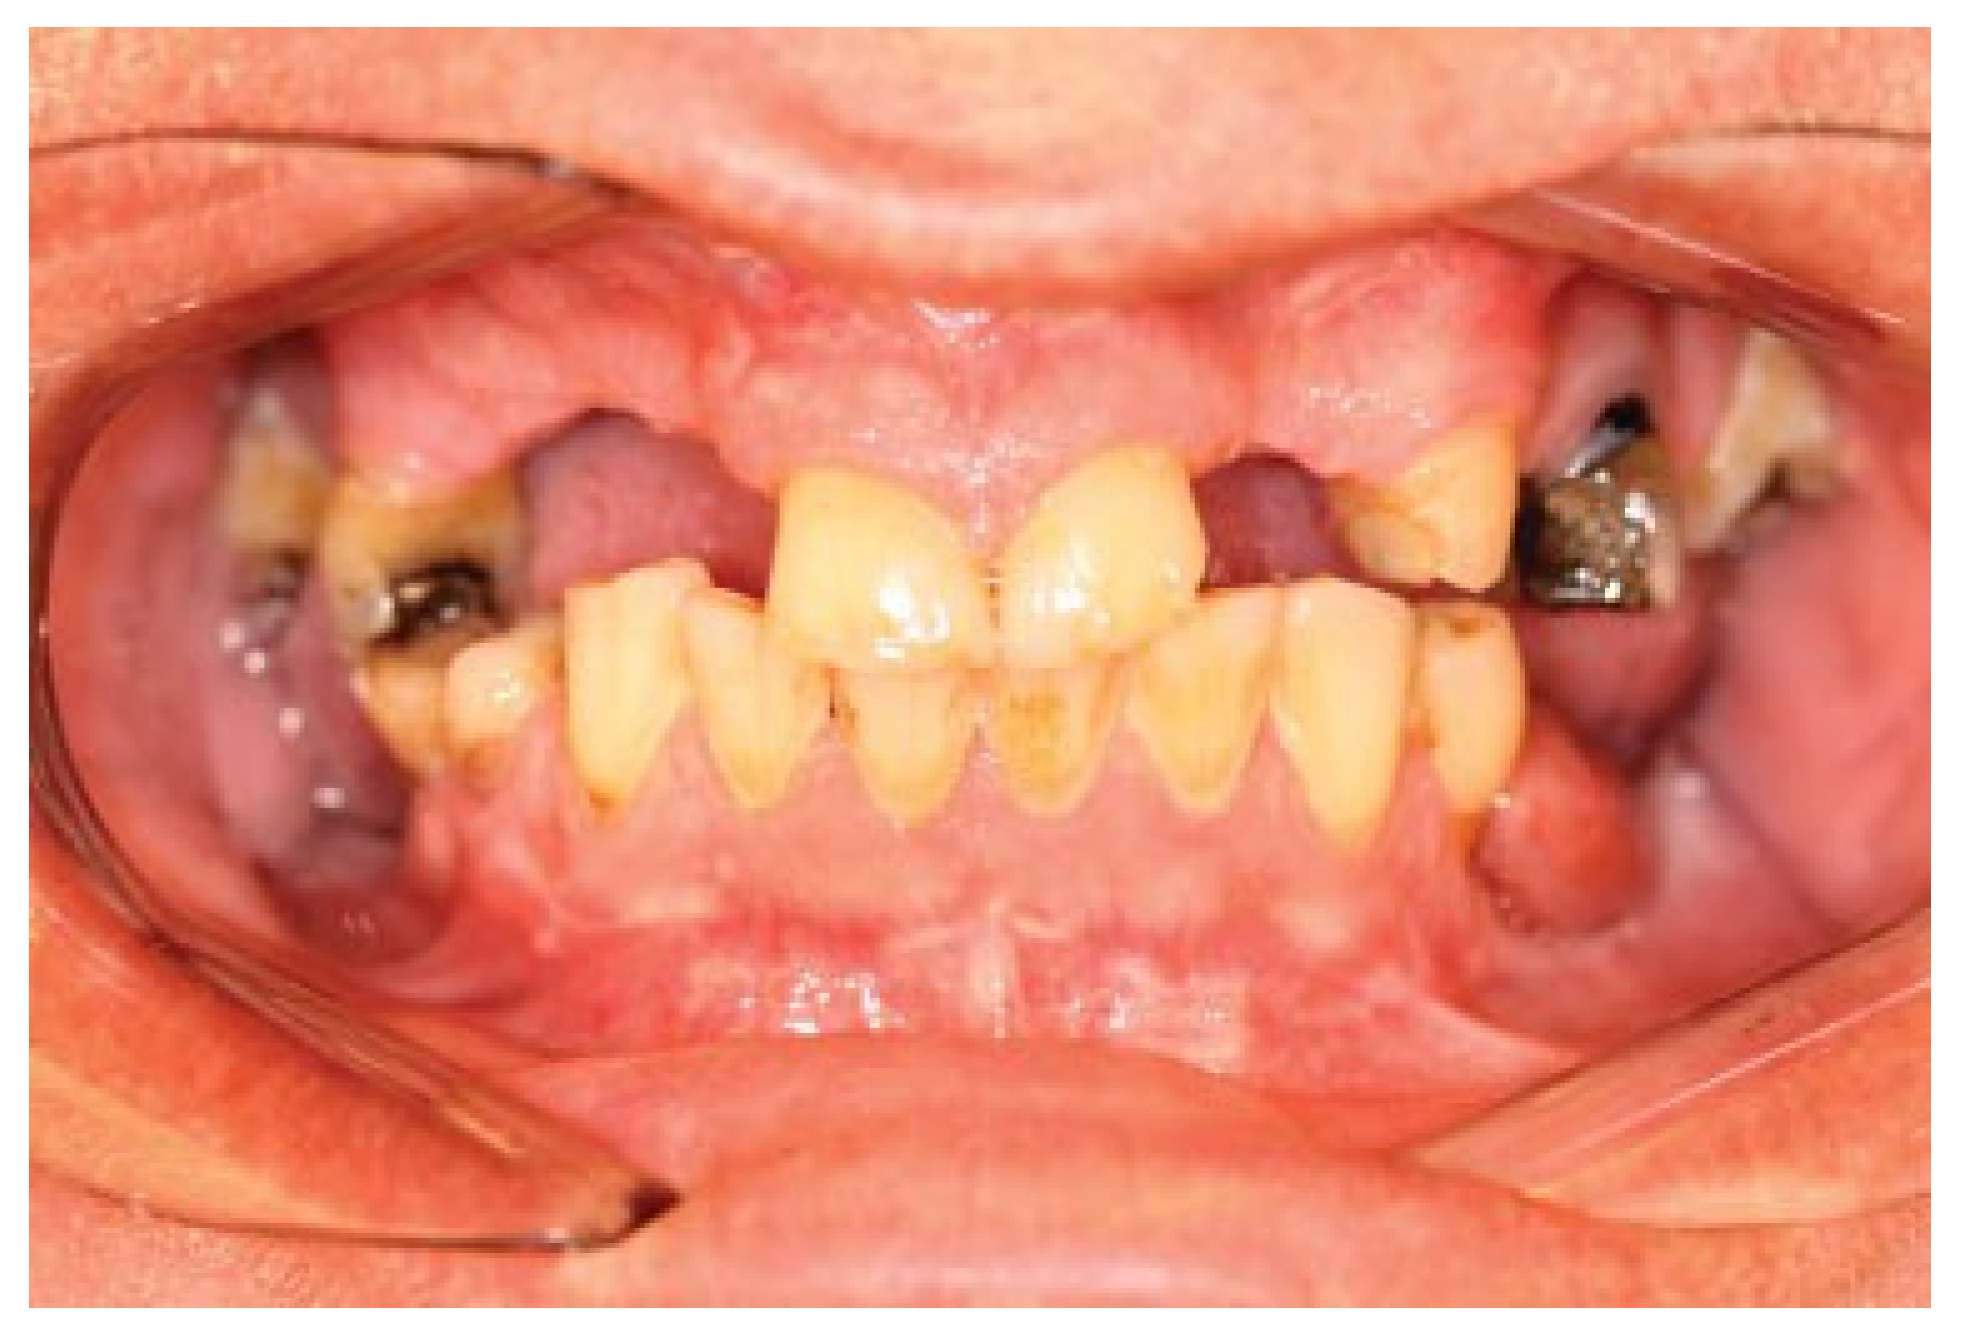

A 57-year-old man sustained a bilateral mandibular body comminute fracture due to a horse-kick trauma to his lower jaw. The subject was obese but otherwise healthy and due to the trauma omitted to the Uppsala University Hospital, Department of Oral & Maxillofacial Surgery. The anterior part of the mandible was severely displaced with a clinical open bite and the subject was taken from the Intensive care unit (ICU) to the Operating room (OR) after one night of monitoring. Partial edentulism was seen in both jaws (Figure 1). Open reduction and fixation of the fractures were performed via an intra-oral route. Noticeable was the difficulty in using a trocar due to the subjects’ constitution with abundance of soft tissue. Two mandibular plates were placed on each side and post-operative situation was evaluated with cone beam computed tomography (CBCT) (Figure 2). Initial healing was uneventful and the patient was not held in maxillo-mandibular fixation (MMF). At the two-week follow-up intraoral fistulas were found in the area of fractures and instability of the osteosynthesis occurred with opening of the bite as a result. The subject was scheduled for secondary surgery and meanwhile oral antibiotics (phenoxymethyl penicillin and metronidazole) were prescribed.

Figure 1.

Preoperative situation. Displaced bilateral mandibular body fracture after trauma by a horse-kick.